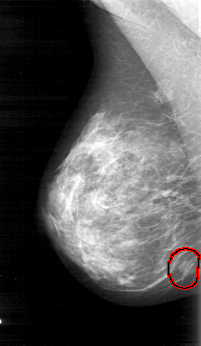

D_4031_1.RIGHT_MLO

FILE: D_4031_1.RIGHT_MLO.OVERLAY

TOTAL_ABNORMALITIES 1

ABNORMALITY 1

LESION_TYPE MASS SHAPE OVAL MARGINS OBSCURED

ASSESSMENT 0

SUBTLETY 5

PATHOLOGY BENIGN

TOTAL_OUTLINES 1

BOUNDARY